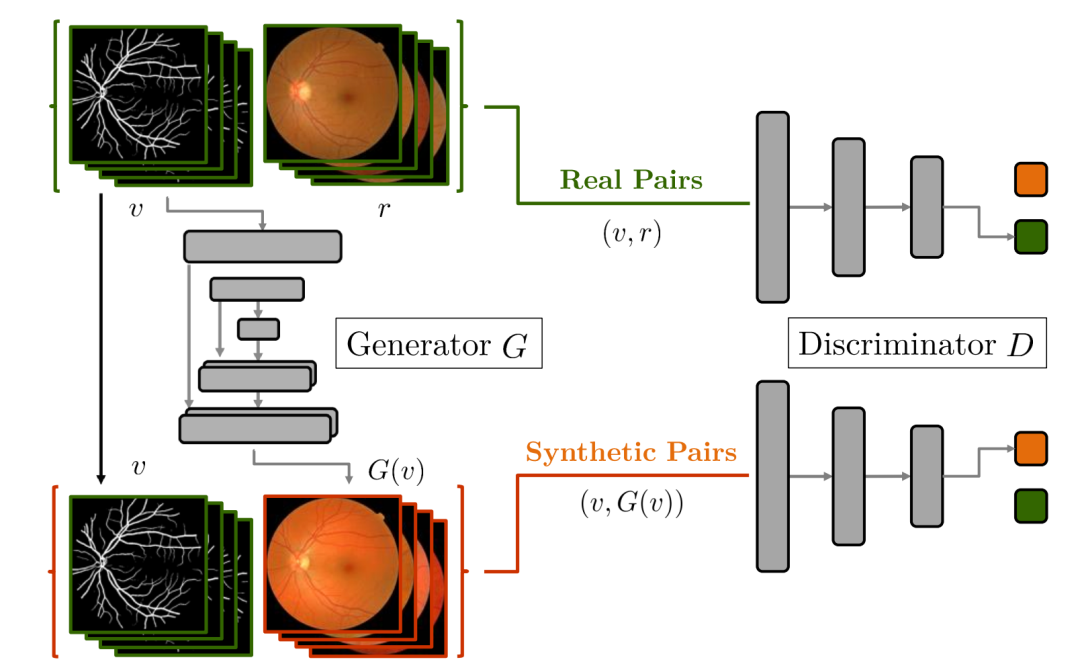

2 有条件监督数据仿真GAN

有些数据的获取对人体会造成一些伤害,比如CT扫描的图片比MRI图片危害性更大,我们可以使用图像翻译框架Pix2Pix将某一个域的数据转换为另一个域的数据,比如MRI变成CT。另一方面,直接生成RGB图像可能受限于训练数据,但是我们可以基于图像翻译框架,从更加简单的数据形式,比如从同一个分割掩膜生成不同的彩色图片,从而实现数据集的扩充。

[4] Nie D, Trullo R, Lian J, et al. Medical image synthesis with context-aware generative adversarial networks[C]//International conference on medical image computing and computer-assisted intervention. Springer, Cham, 2017: 417-425.

[5] Costa P, Galdran A, Meyer M I, et al. End-to-end adversarial retinal image synthesis[J]. IEEE transactions on medical imaging, 2017, 37(3): 781-791.